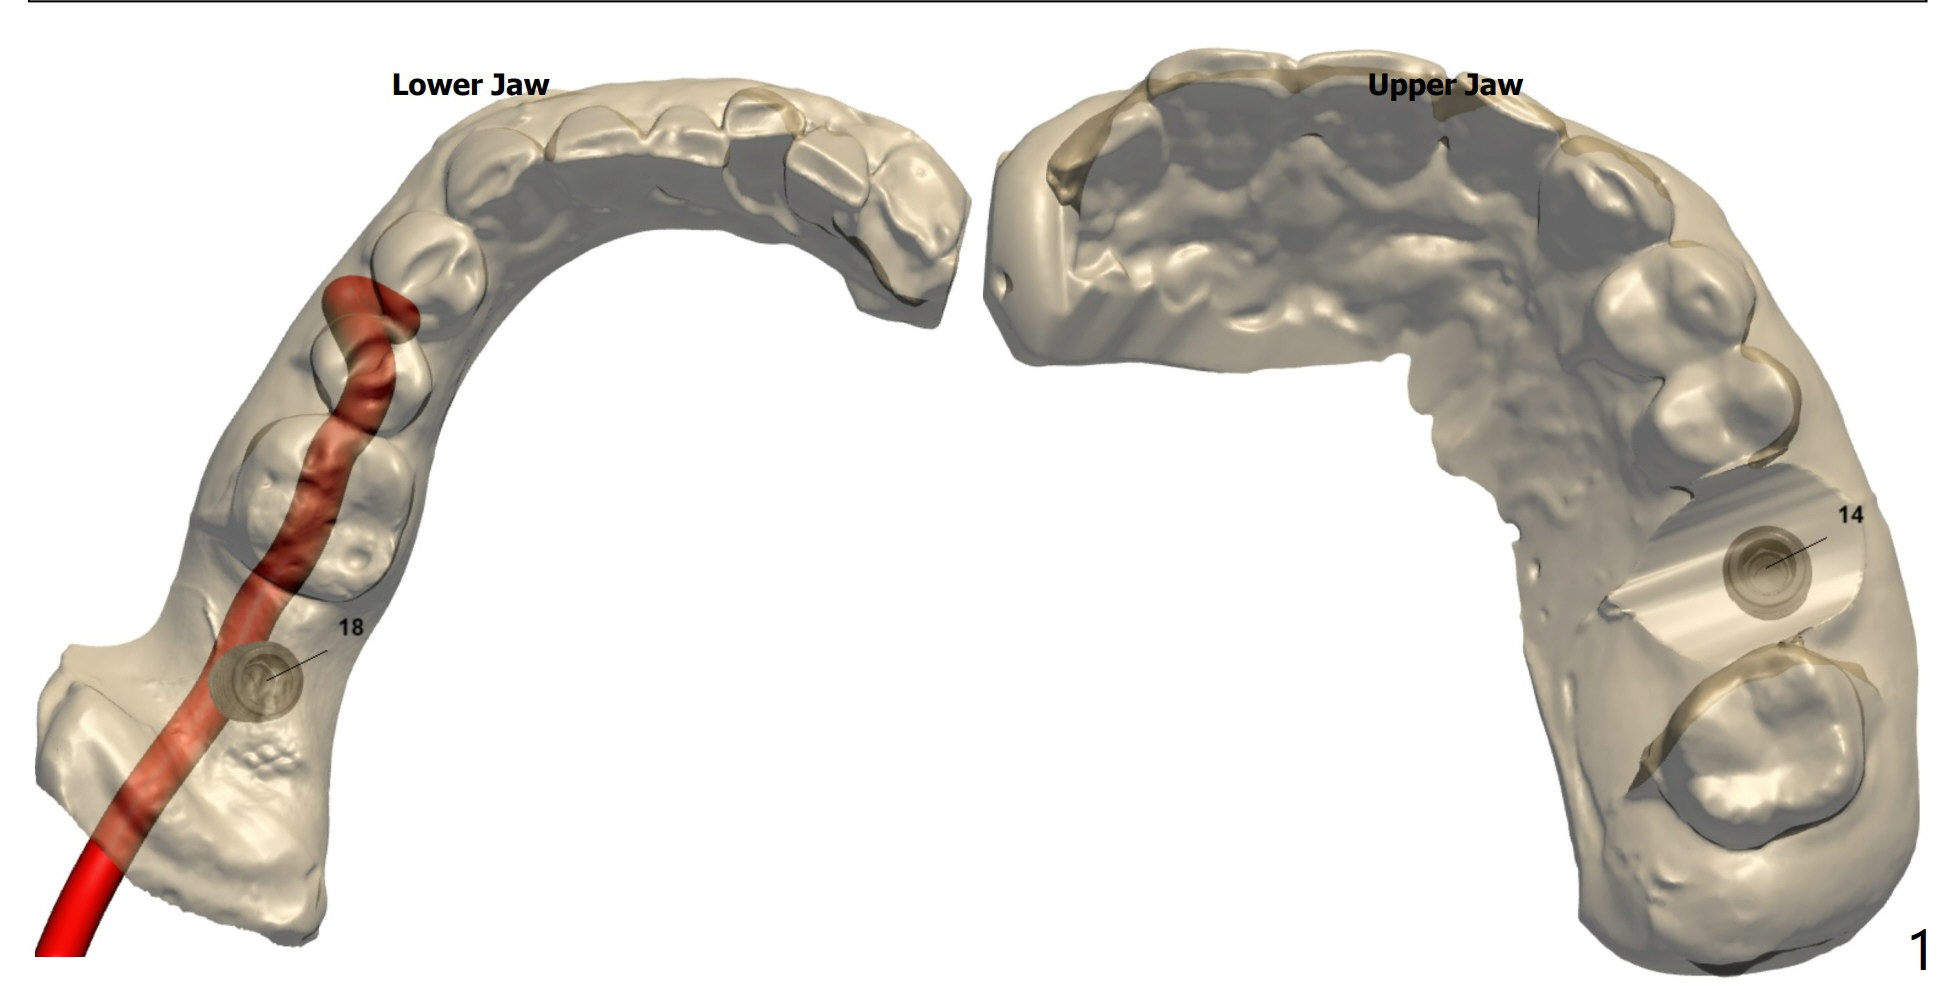

Short Implants

PRFx1 (18 14)

Return to Prevent Molar Periimplantitis (Protocols, Table) No Caries Metronidazole  第二磨牙即种